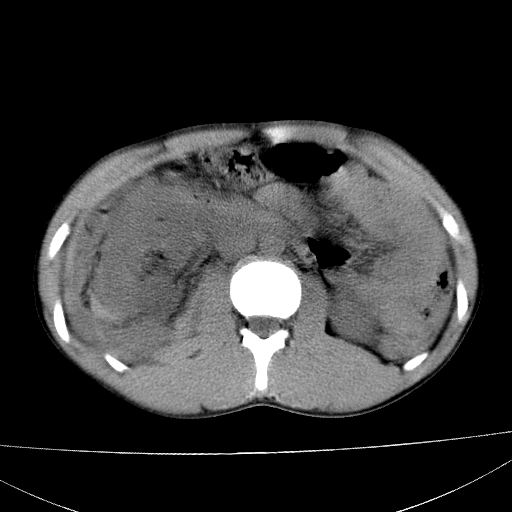

肝脏及肾脏明显有损伤性改变并激发腹腔内积液(血),以肝脏撕裂及肾周积血显著。

1)肝破裂伴腹腔积液(血)。2)右肾破裂伴右肾包膜下及肾周血肿。3)腹部空腔脏器穿孔可能。4)右侧少量胸腔积液(血)。

1)肝破裂伴腹腔积液(血)。2)右肾破裂伴右肾包膜下及肾周血肿。3)右侧少量胸腔积液(血)。

肝肾挫裂伤,右肾周及包膜下血肿,腹腔积液,不排除空腔脏器穿孔,建议行增强检查

1肝挫伤伴腹腔积液。2右肾挫裂伤伴右肾包膜及肾后间隙肿血肿。3右肾脏周围的积气,十二指肠显示结构不清,考虑十二指肠降部破裂可能性大。